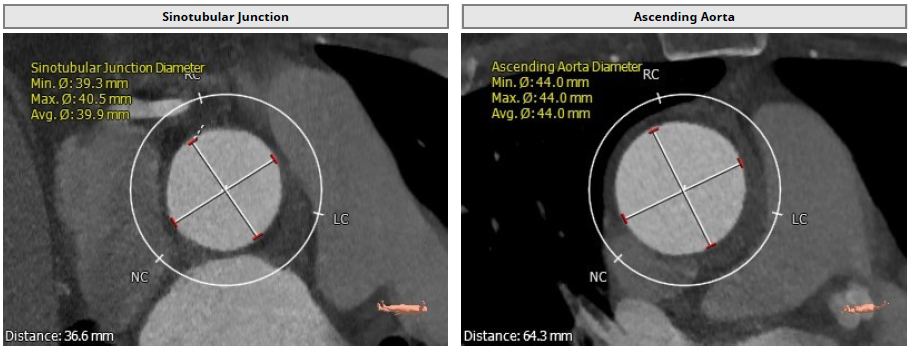

Annulus: 30.1mm

环上结构折算直径:30.3mm ;主动脉瓣环夹角:135°

LVOT: 31.5mm;窦部直径:42.7/42.0/46.9mm

窦管交界:39.9mm;升主动脉:44mm